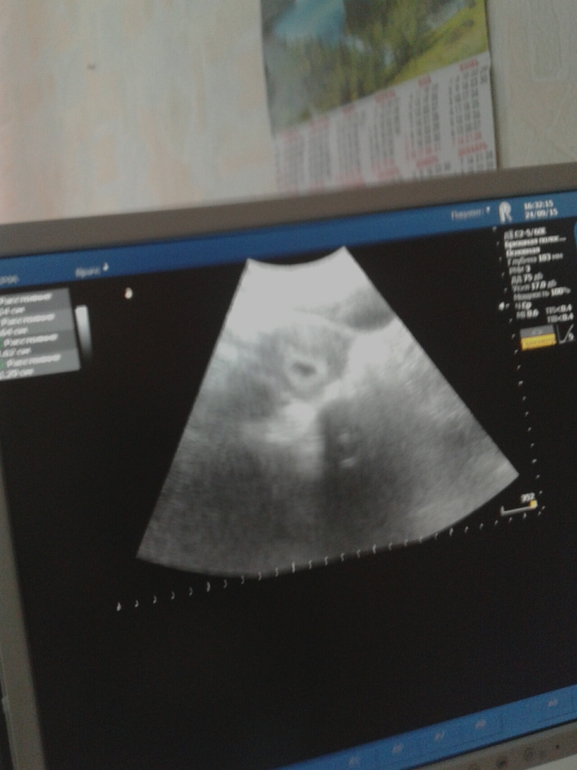

вот вам вторая фотка детёныша! )))